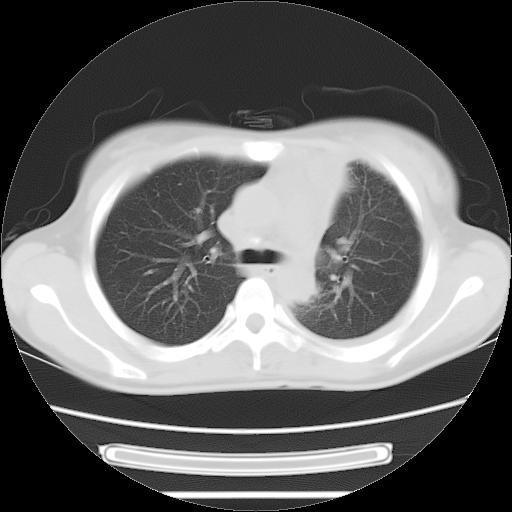

女,29岁,胸部不适,在外院胸片提示胸腔积液,到我院ct检查。

肺窗:

1、左侧包裹性积液伴叶间积液 2、右肺多发结节考虑增殖结节

考虑:1.两肺tb;2.左侧胸膜炎、胸腔积液。

考虑两肺结核,左侧包裹性积液,叶间积液。

右肺多发结节。左胸腔多发包裹性积液。